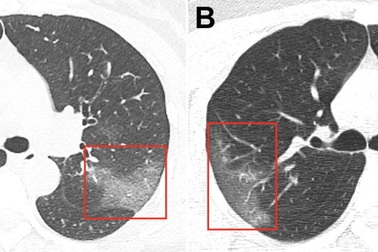

Công bố ảnh chụp lá phổi bị ảnh hưởng bởi vi rút corona mớiCác chuyên gia y tế Trung Quốc đã công bố bức ảnh chụp phổi của một bệnh nhân bị nhiễm coronavirus 2019 (nCoV).